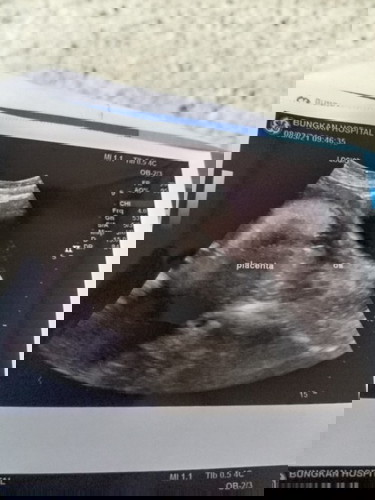

อ่านเพิ่มเติมหมอบอกรกเกาะต่ำ เหมือนกันค่ะ ต้องได้ผ่าคลอด ตอนนี้ 29 สัปดาห์ ค่ะ หมอให้ระวังเรื่องเลือดออกค่ะ